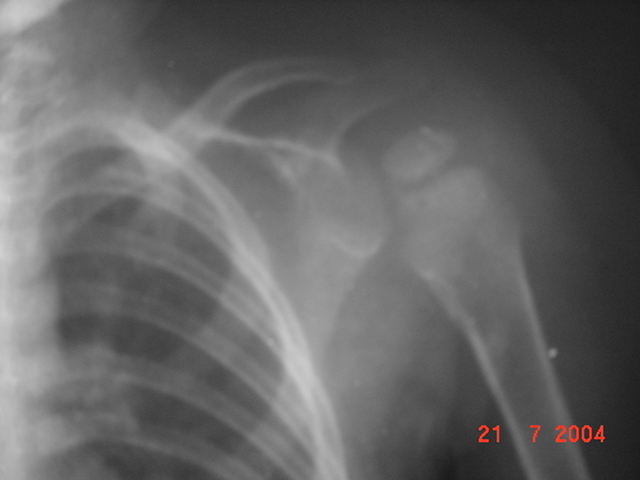

LUXACIÓN HOMBRO IZQUIERDO

Niña de 1 año que la madre le da tirón de la mano izquierda. Dolor y falta de movimiento del miembro. Se le toman Rx. Por llorar mucho la madre la chinea y la toma por las axilas. Se le quita el llanto. Se le manda Rx de control. |

Control post reducción por la madre